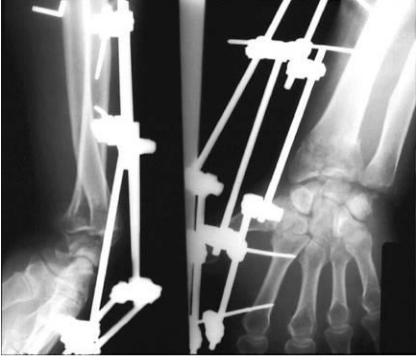

• 儿童骨折保守治疗,长时间外固定,上肢4周,下肢6~8周

长期固定使得血液循环和淋巴组织液回流受阻,关节腔内滑液流动减慢,使得血液及滑液循环发生改变,组织和肌肉间形成水肿,发生粘连,同时关节囊和韧带等组织因缺血出现营养不良、挛缩、活动受限,进而影响关节活动,促进关节挛缩的发生、发展。

• 由于疼痛或缺乏及时的康复指导,术后患儿损伤关节活动减少

• 关节周围严重的软组织损伤,炎症失控,疤痕形成